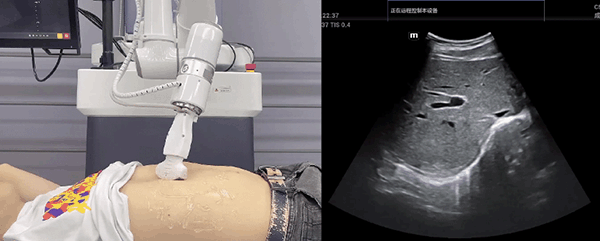

艾利特機(jī)器人末端搭載超聲探頭,可以對淺表小器官和外周血管、腹部(肝、膽、胰、腎等器官)進(jìn)行超聲檢查。

目前,艾利特機(jī)器人在生物醫(yī)藥、醫(yī)療健康領(lǐng)域的賦能已有顯著進(jìn)展,艾利特協(xié)作機(jī)器人應(yīng)用場景覆蓋了臨床試驗(yàn)、試管檢測、拭子采集、試管搬運(yùn)、熒光檢測、康復(fù)治療、超聲掃查、導(dǎo)診、消毒、微創(chuàng)治療、針灸刮痧等。